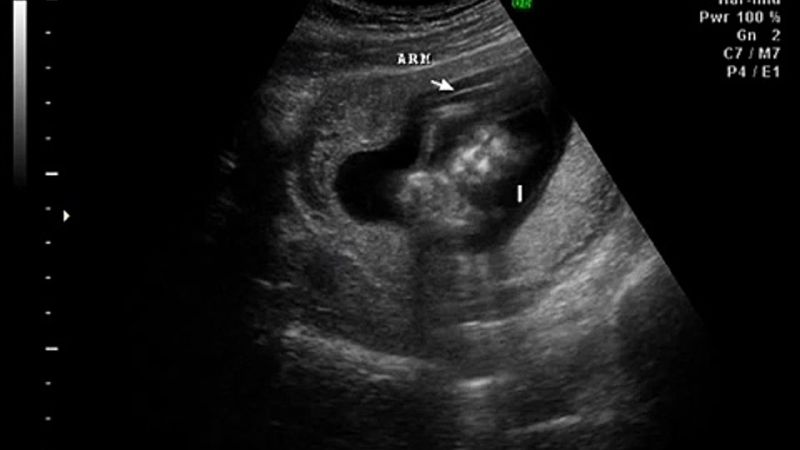

وقد ظهر جهاز حديث يسمى السونار للكشف عن عمر الحمل وحالة الجنين وجنسه، يستخدم جهاز السونار لإنشاء صورة ثنائية الأبعاد على شاشة الكمبيوتر، يستمر حوالى عشرين دقيقة، ويعطي معلومات عن عمر الحمل وتقييم الجنين، يقيس هذا الاختبار حركة تدفق الدم والسرعة التي ينتقل فيها الدم في الرحم أو الحبل السري أو في قلب الجنين أو حول جسمه، سنتعرف في هذا المقال عن الوقت الذي يمكننا فيه معرفة جنس الجنين، وهل يخطئ السونار في تحديد نوع الجنين في الأسبوع 12.

- كما أكدوا أن السونار يكشف جنس الجنين بالبحث عن بعض العلامات، وباستخدام الموجات فوق الصوتية.